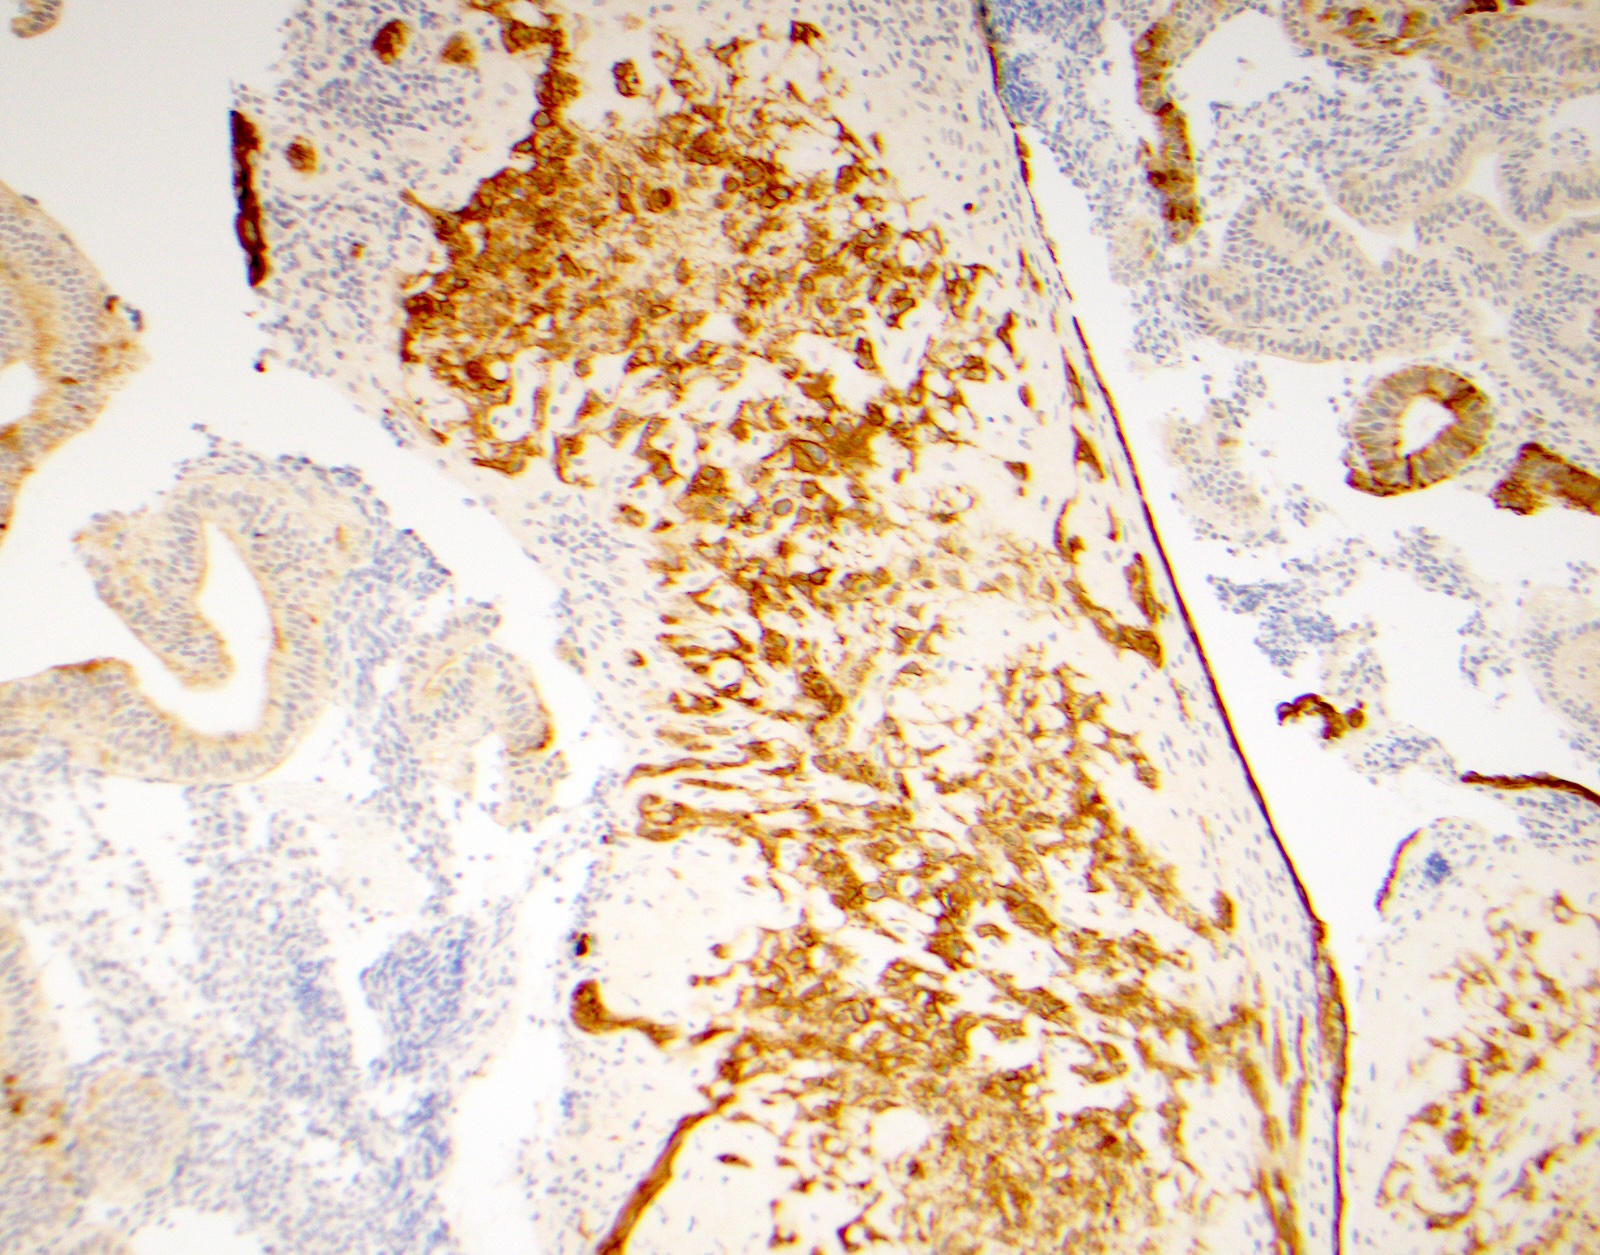

Microscopic (histologic) images

Contributed by Surekha Bantumilli, M.D. and Dimitri G. Trembath, M.D., Ph.D.

Positive staining - normal

- Prostate basal cells, skin (J Exp Clin Cancer Res 2003;22:441)

- Identification of the basal cell layer in prostate tissue in the determination of carcinoma

Practice question #1

A 65 year old man presents with elevated prostate specific antigen (PSA) and undergoes a prostate biopsy, stained with high molecular weight cytokeratin (HMWCK) (shown above). What is the most likely interpretation of this staining pattern?

- Benign prostate tissue

- Benign seminal vesicle

- High grade prostatic intraepithelial neoplasia

- Prostatic adenocarcinoma

- Urothelial carcinoma

Practice answer #1

A. Benign prostate tissue. The basal layer of benign prostate glands will stain with high molecular weight cytokeratin. Answer D is incorrect because staining will be lost on prostatic adenocarcinoma. Answer C is incorrect because high molecular weight cytokeratin staining can be present in high grade prostatic intraepithelial neoplasia but is not diagnostic by itself for this entity. Answers B and E are incorrect because the glandular appearance outlined by the high molecular weight cytokeratin staining is not consistent with either seminal vesicle or urothelial carcinoma.